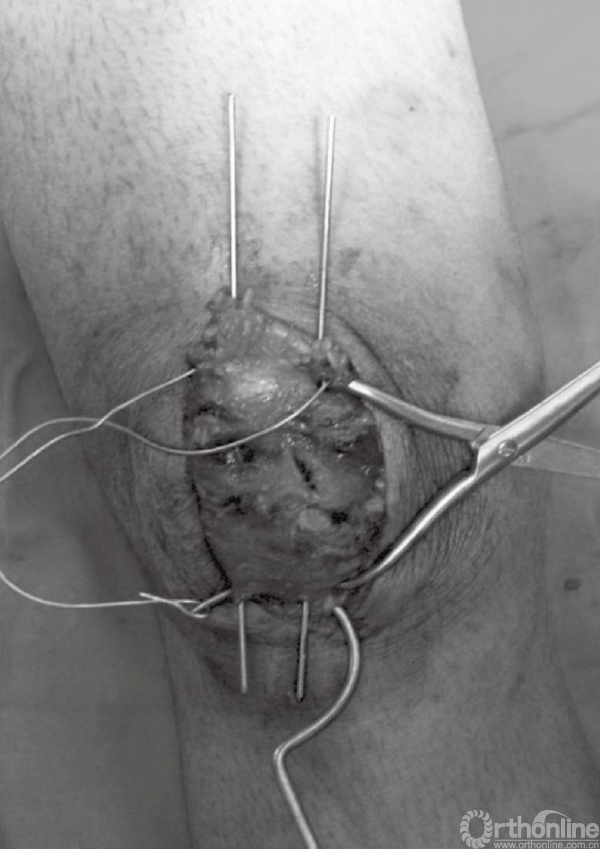

应仔细探查关节,以辨识游离骨块以及关节面损伤(图6)。此时,可对骨折进行复位,并以复位钳进行临时固定。检查骨折复位情况以及关节稳定性,关节内骨块的解剖复位是非常重要的。术中复位困难,可能是因为小骨块或者软组织嵌于骨折端。

图6 应仔细探查关节以辨识游离骨块以及关节面损伤